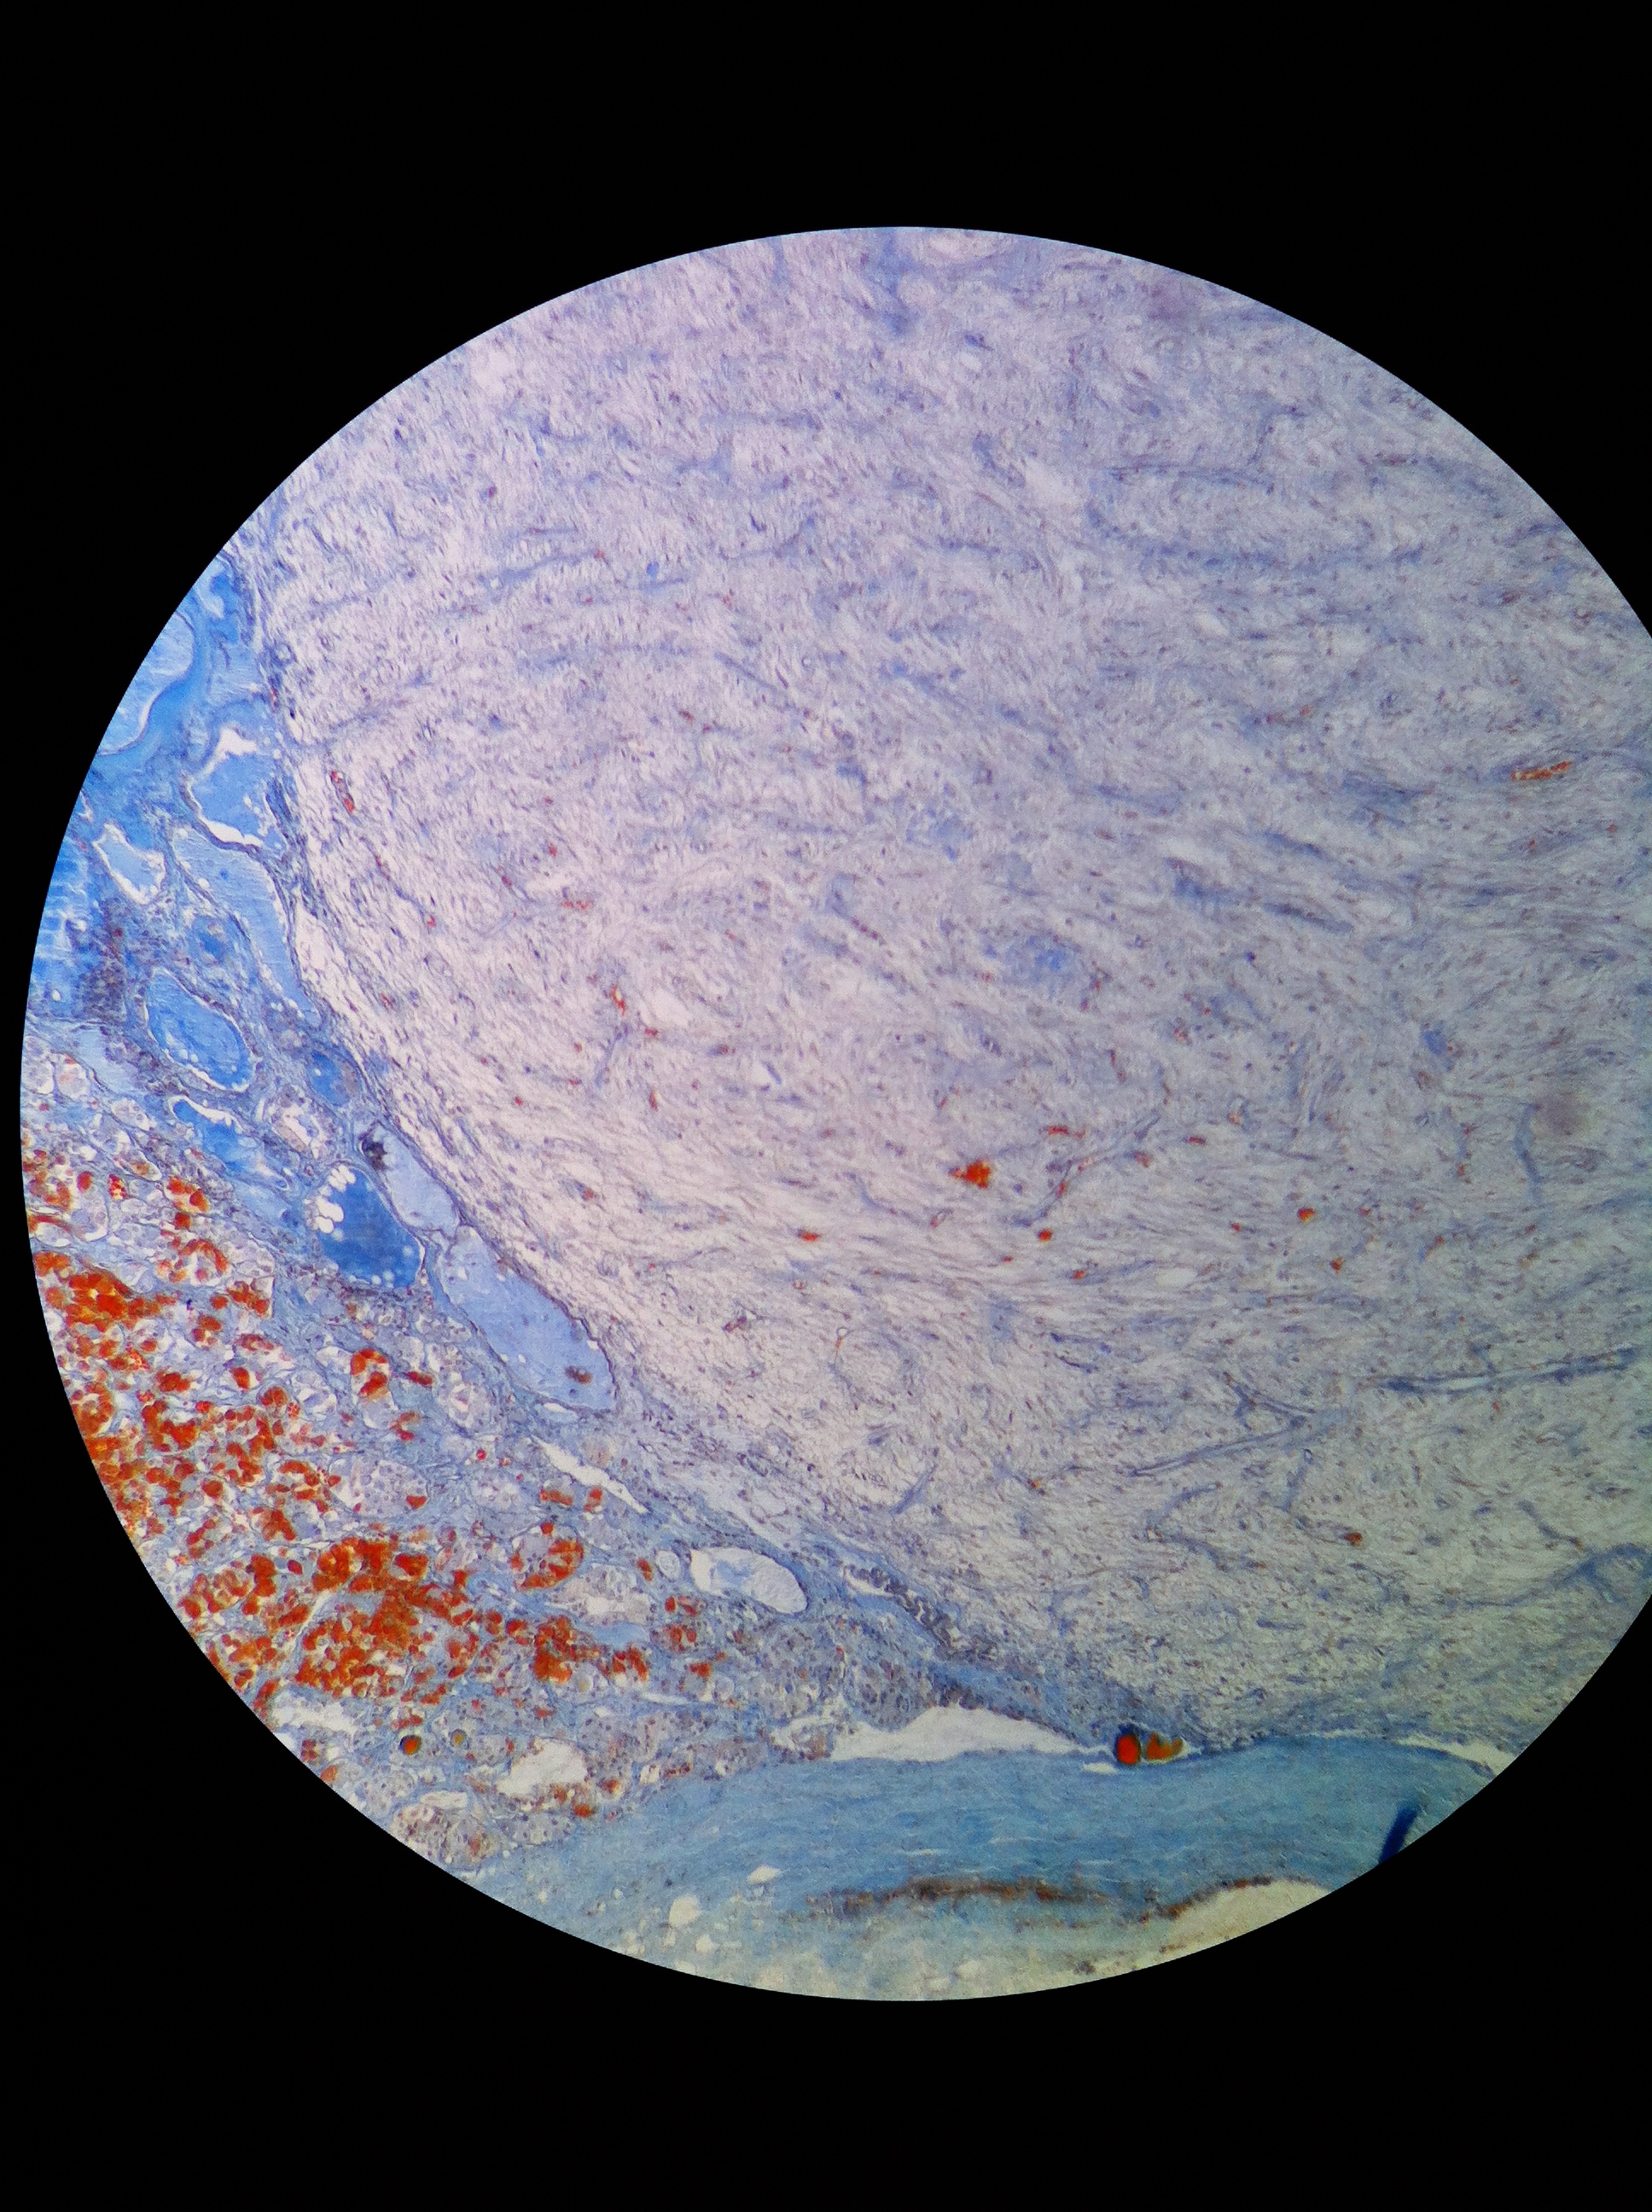

Adrenal Cortex 40X

Adrenal Cortex 100X